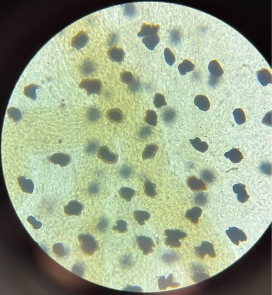

Uniocular Adipose Tissue (White Adipose)